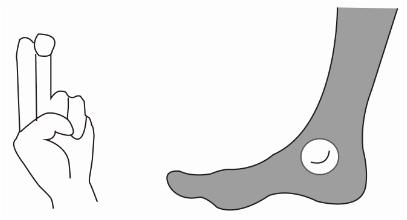

二、跟骨骨密度儀檢測時足和身體的位置

檢測時,足緊貼于產品的最下端(如圖緊貼3個部位)。 骨密度儀的護腿板與足軸和身體的中心軸,需呈一條直線。

跟骨骨密度檢測正確坐姿示意圖